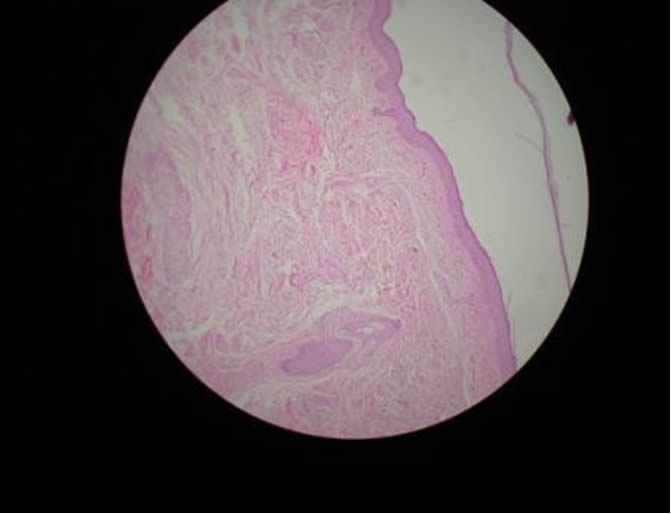

OCRONOSIS EXOGENA

OCRONOSIS - HISTOPATOLOGIA - DR. PIQUERO